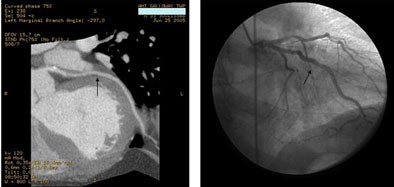

![]() |

| A 59-year-old woman presenting with chest pain had a normal CTA, as shown below right with visualization of the atrioventricular nodal branch. |